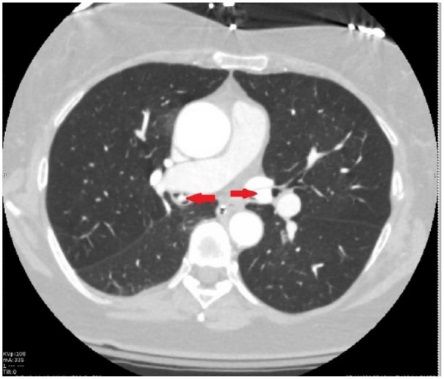

Пациентка обратилась с жалобами на прогрессирующую одышку и кашель в течение месяца. Рентгенография органов грудной клетки показала изменения в правом легком с небольшим количеством жидкости в правой плевральной полости. Но при компьютерной томографии грудной клетки инфильтрации или других изменений легочной ткани не обнаружено. Пациентке назначена эмпирическая антибактериальная терапия. При исследовании мокроты выявлен рост непатогенной флоры. Состояние пациентки продолжало ухудшаться, что потребовало интубации трахеи и искусственной вентиляции легких. При повторной КТ грудной клетки выявлены гиперденсные образования в просвете левого главного (размер 2,2 см) и промежуточного бронхов (размер 1,5 см), обтурирующие их (рис. 1, 2).

Рисунок 2 [1].